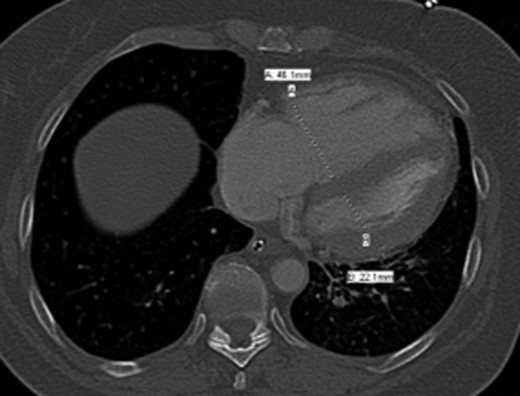

Once stable, imaging confirmed PE (Fig. 2) with a RV to left ventricle (LV) ratio of 2.1 (Fig. 3). The patient was then admitted to the ICU requiring inotropic support. Approximately 4 h later, the patient had concerning features of abdominal compartmental syndrome with increase abdominal distention and bladder pressures >25 mmHg was noted. Repeat imaging showed large volume hemoperitoneum emanating from the left hepatic lobe (Fig. 4). The patient underwent a decompressive laparotomy with a non-anatomic liver resection of segments I and II and temporary abdominal closure. Due to concerns of distal limb ischemia of the arterial cannulation site, an 8-Fr reperfusion cannula was placed in the left superficial femoral artery (SFA).

CTA chest demonstrating significant RV strain with a RV/LV ratio of 2.1.